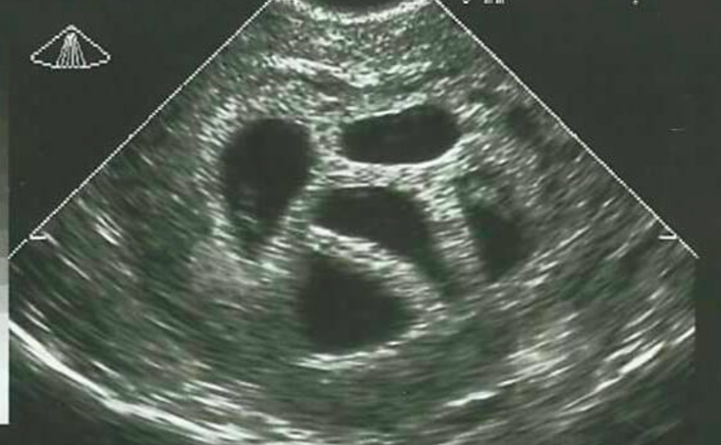

Selective reduction

Selective reduction means that one or more embryos or foetuses are killed and/or removed to increase the chances of survival for the other(s). When Susan refused to do this, the doctor sent her to a specialist, who also tried to convince her to continue her pregnancy with only a selection of the embryos. Nevertheless, Susan and her husband stuck with their decision. It was the best decision they could have made!